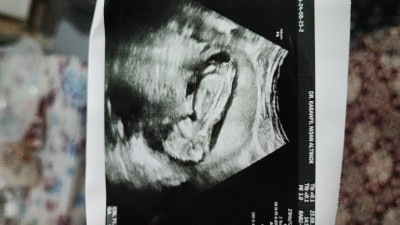

Kizlar doktor erkeğe benzettim dedi ama emin olmadı ilk yavrum oğlan . Tabiki sağlıklı olsun da olmayan istenir siz ne düşünüyorsunuz

Erkek sanki. Allah bilir yine

Bakar bakmaz erkek dedim